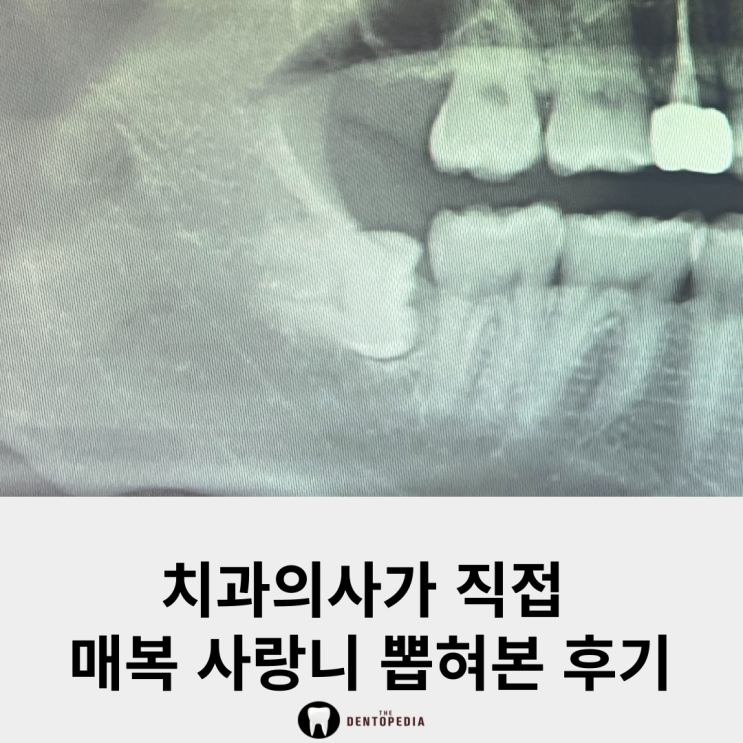

사랑니 발치 고통 치과의사가 직접 뽑혀본 후기

여러분들은 사랑니를 혹시 뽑으셨나요? 저는 아래쪽 사랑니를 아직 안 뽑고 있다 이번에 동료 치과의사분께...